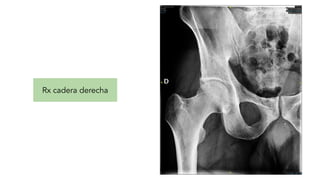

Rx cadera derecha

Pruebas complementarias Analítica Rxtórax Rx cadera derecha TC Craneal Hemocultivos Urocultivo